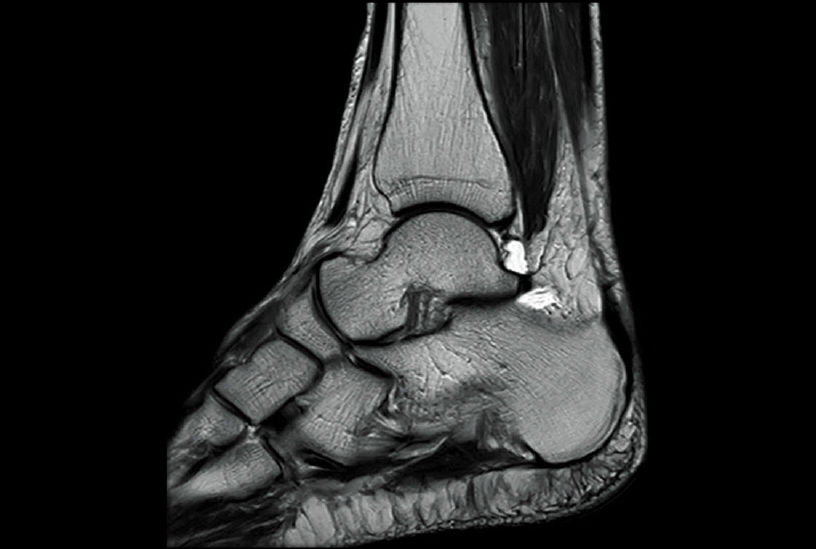

Клинические изображения аппарата МРТ Fujifilm ECHELON Smart

Fujifilm ECHELON Smart — это современная система магнитно-резонансной томографии 1.5 Тесла, спроектированная для достижения оптимального баланса между качеством изображения, скоростью исследования, комфортом пациента и экономичностью эксплуатации. Аппарат МРТ объединяет в себе инженерные традиции японской школы точного машиностроения и инновационные алгоритмы обработки изображений Fujifilm, создавая мощную платформу для широкого спектра клинических задач — от нейровизуализации и сосудистых исследований до МРТ брюшной полости, суставов и позвоночника. Томограф построен на базе высокопроизводительных подсистем SmartENGINE, SmartSPEED, SmartQUALITY и SmartCOMFORT, обеспечивающих стабильную работу, высокую чувствительность и превосходное соотношение сигнал/шум при низких эксплуатационных затратах.